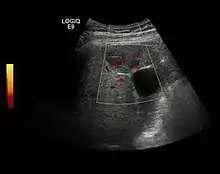

Benign focal nodular hyperplasia (CEUS). Gray scale examination (left) detects the lesion. CEUS examination (right) allows characterization of tumor nature based on central contrast enhancement and centrifugal dispersion.

It is a tumor developed secondary to a circulatory abnormality with abundant arterial vessels having a characteristic location in the center of the tumor, within a fibrotic scar. A radial vessels network develops from this level with peripheral orientation. The tumor's circulatory bed is rich in microcirculatory and portal venous elements. The incidence is higher in younger women and tumor development is accelerated by oral contraceptives intake. 2D ultrasound appearance is a fairly well-defined mass, with variable sizes, usually single, solid consistency with inhomogeneous structure. Rarely the central scar can be distinguished. Spectral Doppler examination detects central arterial vessels and CFM exploration reveals their radial position. CEUS examination shows central tumor filling of the circulatory bed during arterial phase and completely enhancement during portal venous phase. During this phase the center of the lesion becomes hypoechoic, enhancing the tumor scar. During the late phase the tumor remains isoechoic to the liver, which strengthens the diagnosis of benign lesion.